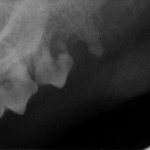

40% kotów cierpi na FORL czyli Feline Odontoclastic Resorptive Lesion. W rutynowym badaniu jamy ustnej choroba ta bardzo często nie daje żadnych objawów.

Najczęściej zaczyna się zwykle w wieku około 5 lat, nie jest to jednak reguła, mogą chorować zwierzęta starsze i młodsze. Ze względu na ekspozycję otwartych kanalików zębinowych oraz miazgi choroba jest bardzo bolesna. Najlepszą formą jej szybkiego diagnozowania jest wykonanie pełnego kompletu zdjęć rentgenowskich jamy ustnej. Każdy kot trafiający na zabieg stomatologiczny, niezależnie od przyczyny, ma wykonywane zdjęcia RTG wszystkich zębów. Cyfrowa radiografia wewnątrzustna pozwala nam to w zaledwie kilka minut uzyskać zdjęcia w doskonałej jakości, umożliwiające diagnozowanie wielu bolesnych problemów w jamie ustnej naszych podopiecznych i wdrożenie właściwego leczenia.